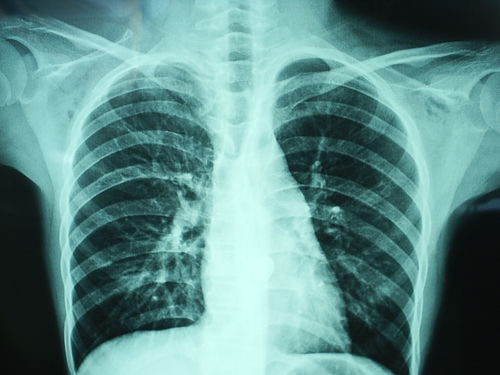

胸透可以看到胸部的軟組織、骨骼(包括胸椎)、縱隔(心臟、大血管、氣管、食管等)、氣管和支氣、胸膜、肺組織等??梢栽\斷肺和氣管的先天性疾病,如發(fā)育異常、肺部的各種炎癥、急慢性支氣管炎、比較明顯的支氣管擴(kuò)張癥、肺氣腫或肺水腫、各型肺結(jié)核、肺腫瘤、胸腔積液、氣胸、縱隔腫瘤、心臟形態(tài)異常等

健康查體最常做的是胸部的X線(xiàn)檢查,最基本的就是胸透。 胸透可以看到胸部的軟組織、骨骼(包括胸椎)、縱隔(心臟、大血管、氣管、食管等)、氣管和支氣、胸膜、肺組織等。

可以診斷肺和氣管的先天性疾病,如發(fā)育異常、肺部的各種炎癥、急慢性支氣管炎、比較明顯的支氣管擴(kuò)張癥、肺氣腫或肺水腫、各型肺結(jié)核、肺腫瘤、胸腔積液、氣胸、縱隔腫瘤、心臟形態(tài)異常等。